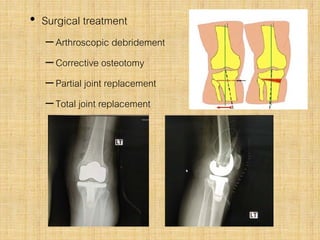

• Surgical treatment

–Arthroscopic debridement

–Corrective osteotomy

–Partial joint replacement

–Total joint replacement

• Surgical treatment –Arthroscopicdebridement –Corrective osteotomy –Partial joint replacement –Total joint replacement